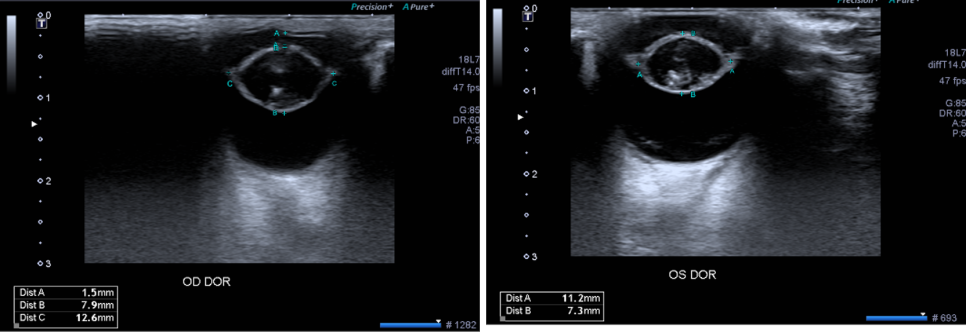

추가로 안과 초음파 검사를 진행하였습니다. 검사 상 백내장이 확인되어 백내장 뒷면에 미약한 초자체의 변성이 확인되었습니다.그 외에는 특이사항이 없었습니다.